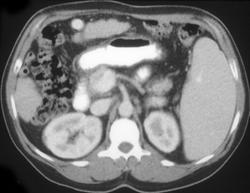

Bacillary Angiomatosis